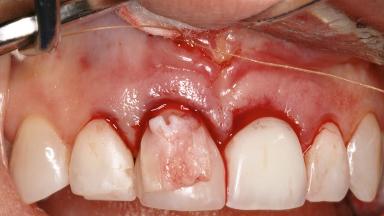

Late Presentation of Peri-Implant Mucositis Requiring Soft-Tissue Augmentation and Esthetic Crown Lengthening at Implant Site 11

Eduardo R Lorenzana, Jason R Gillespie

Biological or technical complications around implant-supported prostheses place a significant burden on patients as well as the surgical and restorative team. Inflammation of the peri-implant soft tissues is often the first sign that something has gone awry. While there is never a good time for a complication, late presentation of inflammation in the soft tissues around a long-standing prosthesis triggers a period of research and review of the case in order to ascertain the treatment history and its possible contribution to the etiology of the situation. This becomes more complicated in situations where a patient has not received regular maintenance and clinical/radiographical examinations due to personal, financial, or professional reasons. When the complication occurs in the esthetic zone, the complexity of the situation expands exponentially, as the only acceptable outcome in the patient’s eyes will be the maintenance of the esthetics of the prosthesis.